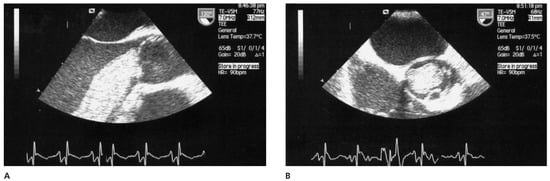

A patient with Morbus Behçet was admitted with severe symptomatic aortic regurgitation caused by aortitis that mimicked infective endocarditis. After aortic valve replacement and antibiotic treatment, regurgitation and systemic inflammation recurred....